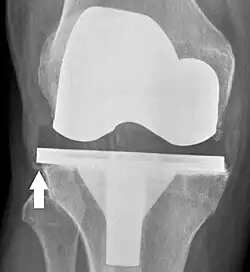

Knee replacement is routinely evaluated by X-ray, including the following measures:

- FFC: frontal femoral component angle. It is typically regarded as optimal when being 2–7° in valgus.[67]

- FTC: frontal tibial component angle, which is regarded as optimal when being at a right angle. A varus position of more than 3° has generally been found to increase the failure rate of the prosthesis.[67]

- Anterior femoral notching (the femoral component causing reduced thickness of the distal femur anteriorly), seems to cause an increased risk of fractures when exceeding about 3 mm.[68]

- LTC: lateral (or sagittal) tibial component angle, which is ideally positioned so that the tibia is 0–7° flexed compared to at a right angle with the tibial plate.[67]